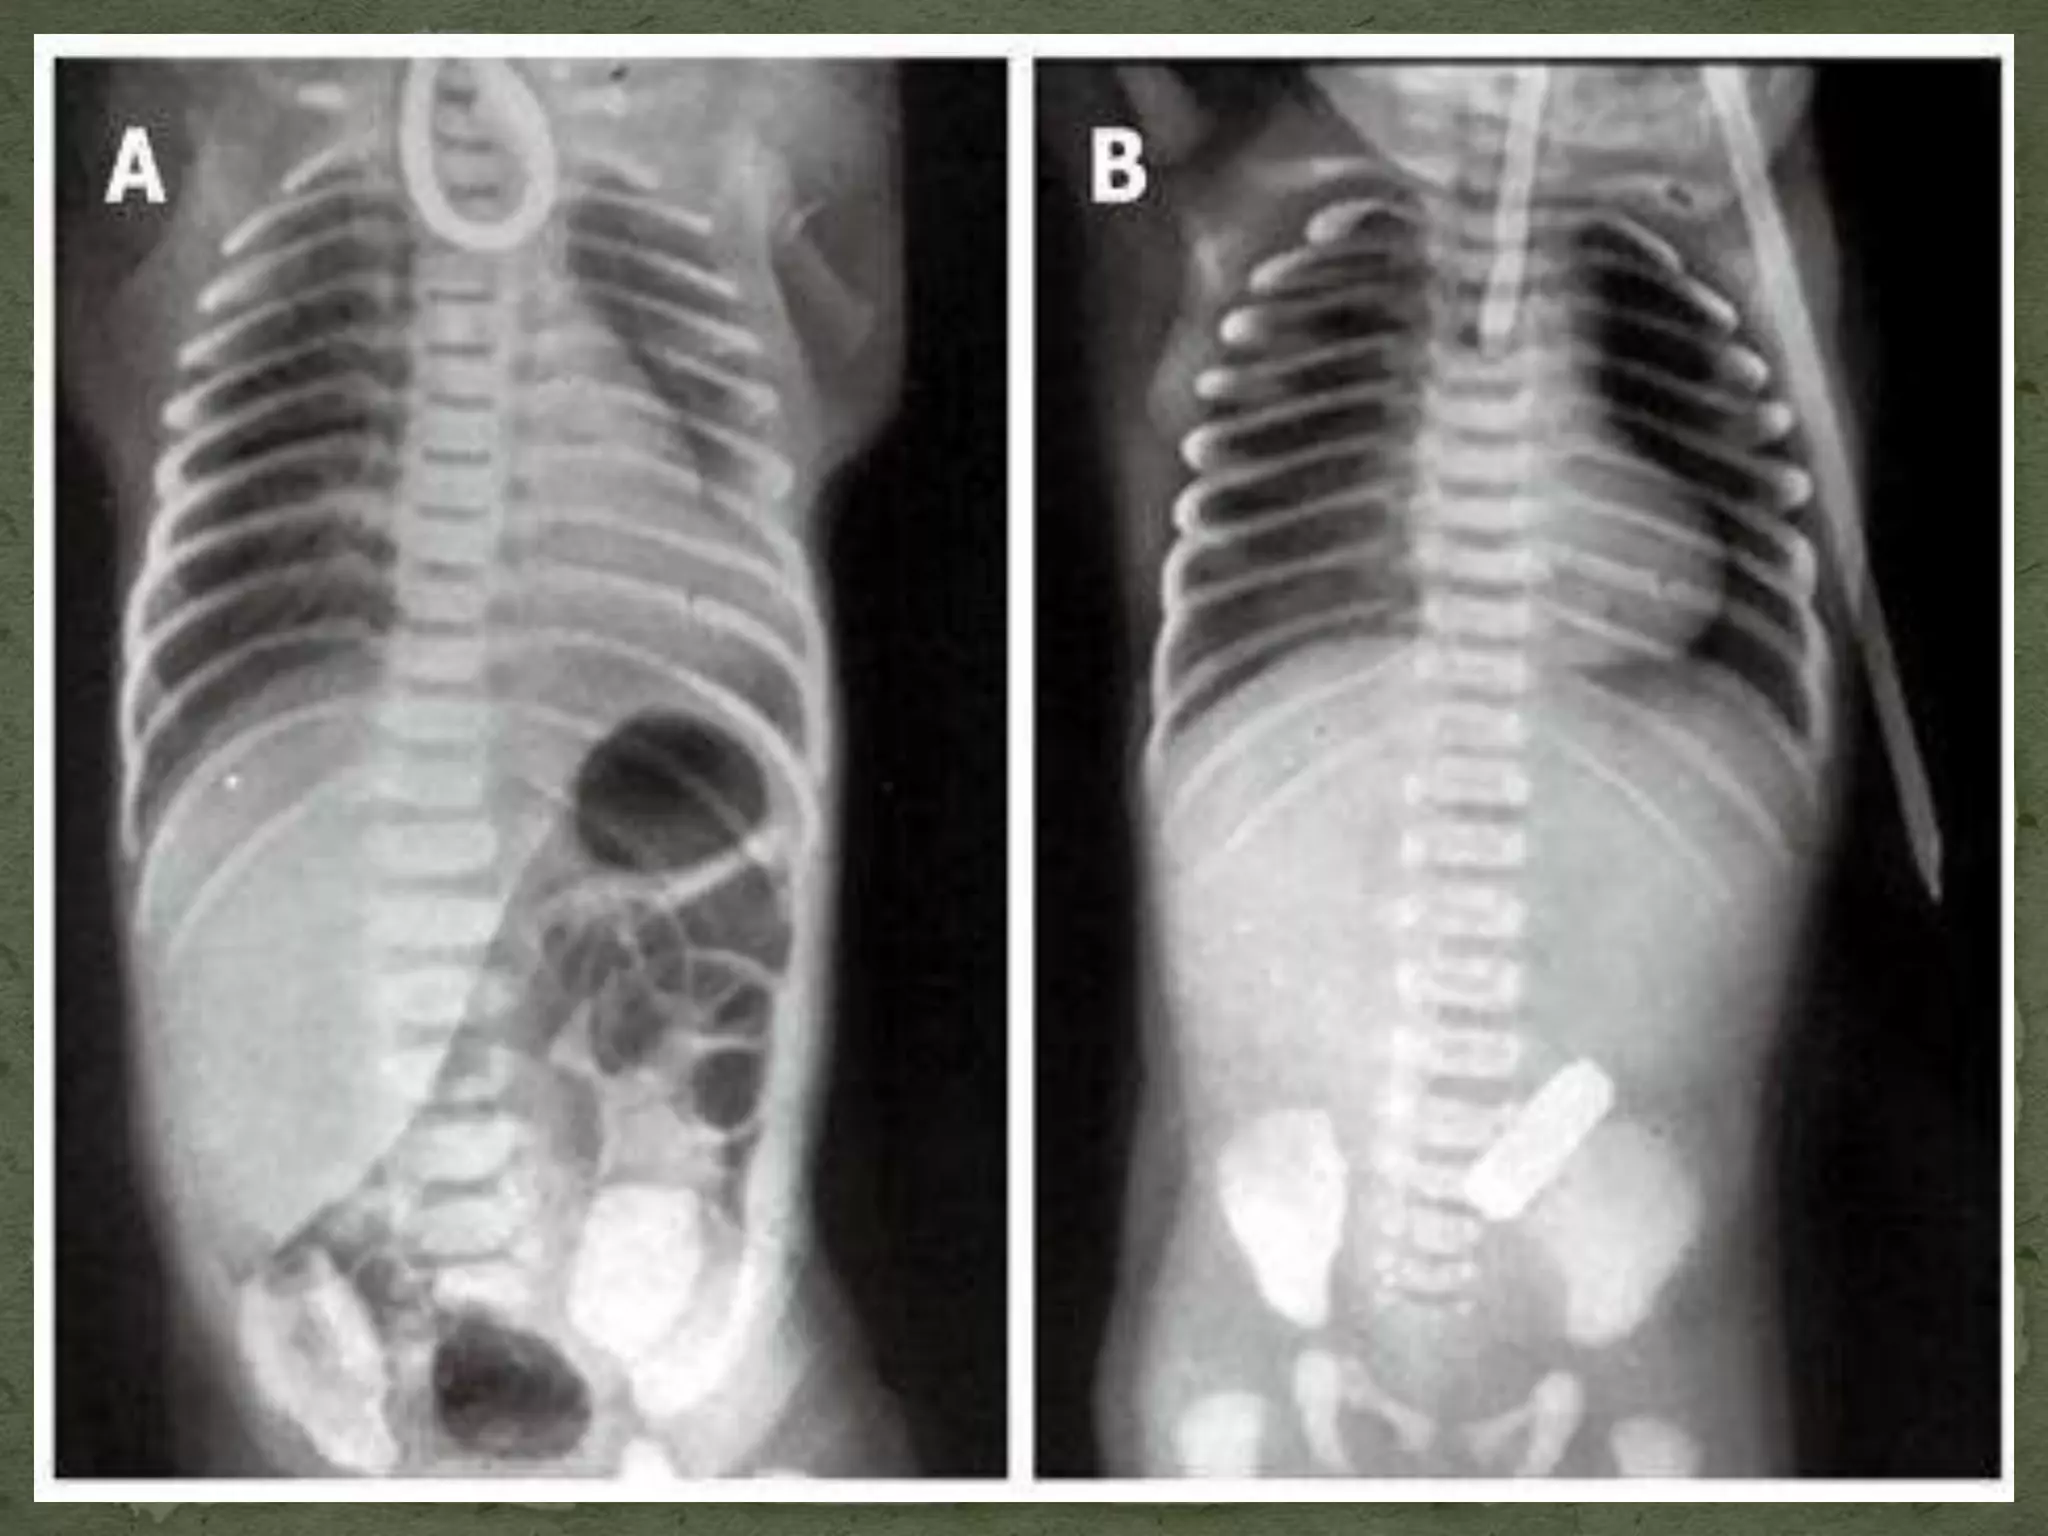

 Laboratory and radiographic evaluation extremely helpful with

pathologic airway

 AP and lateral films and fluoroscopy may show site and cause of

upper airway obstruction

 MRI/CT more reliable for evaluating neck masses, congenital

anomalies of the lower airway and vascular system

 Perform radiograph exam only when there is no immediate threat

to the child’s safety and in the presence of skilled personnel with

appropriate equipment to manage the airway

 Intubation must not be postponed to obtain radiographic

diagnosis when the patient is severely compromised.

 Blood gases are helpful in assessing the degree of physiologic

compromise; however, performing an arterial puncture on a

stressed child may aggravate the underlying airway obstruction